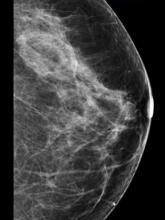

In addition to women with dense breasts, there are also other women for whom mammographic screening is not really enough, which is why research needs to continue in this field. Dr. Wendie Berg, a leading breast cancer specialist, talks with ITN about new research and advancements in breast imaging technology.

Dr. Berg, MD, PhD, FACR, FSBI, is Professor of Radiology at the University of Pittsburgh School of Medicine and Magee-Womens Hospital of UPMC, specializing in breast imaging. She is also the Chief Scientific Advisor to DenseBreast-info.org. A renowned expert, she writes and co-edits one of the leading textbooks on the topic, Diagnostic Imaging: Breast, currently in its third edition, and has co-authored over 120 peer-reviewed research publications.

Breast Density | April 14, 2023

It has long been said that a national reporting standard is needed in order to ensure all American women receive at least the same basic information regarding breast density, and a spotlight put on the importance of routine breast imaging. Dr. Wendie Berg, a leading breast cancer specialist, shares with ITN what is being done in the fight against breast cancer and the importance of this standardization in reporting for women.